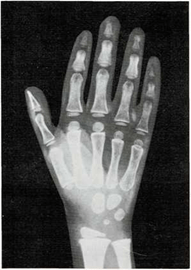

Mi madre me respondió: “Una razón de que lo encuentres blando es que sus huesos no son tan duros como los tuyos. Los niños, al nacer, tienen muy pocos huesos duros. Los huesos de su esqueleto se componen sobre todo de cartílago. Pero las células óseas trabajan sin descanso, y por ello sus huesos crecen y se endurecen muy deprisa. Tus huesos son más largos y duros que los del niño. Los huesos seguirán creciendo y se endurecerán hasta tus veinte años.

El médico me respondió: “Tu muñeca tiene ocho huesos. Pero no todos crecen a la vez. Los huesos de la muñeca de algunos niños crecen más deprisa o más despacio que los de otros niños. Pero los huesos de la muñeca crecen a un mismo ritmo en todos los niños sanos. Si los huesos de tu muñeca salen bien en la radiografía, quiere decir que el resto de los huesos de tu cuerpo también están bien.”

En ella ya se ven claramente los ocho huesos.